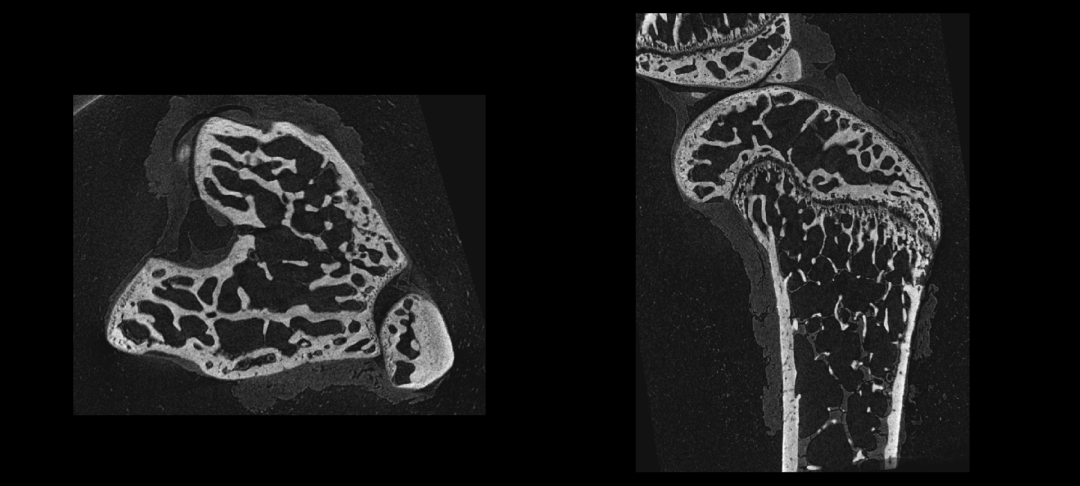

IMAGING 100 软件系统中骨分析模块,具有自动分割皮质骨和骨小梁功能,可在图像上选择感兴趣区域(Region of interest,ROI)做阈值分割等操作,分割皮质骨和松质骨,分别提取不同组织区域,从而对皮质骨和松质骨的各种形态学特性进行研究和分析。

2D及3D骨小梁和皮质骨分割提取

骨参数计算